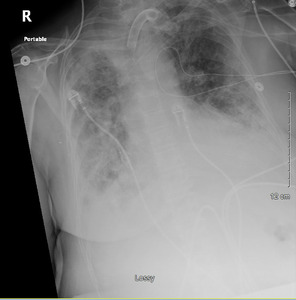

A 66-year-old female with no significant past medical history presented to the emergency department (ED) with a chief complaint of shortness of breath. She presented after approximately one week of symptoms with malaise, fatigue, and cough. On examination, she appeared anxious and in moderate distress with a respiratory rate of 39 breaths per minute (bpm) and pulse oxygen saturation (SpO2) of 81% on room air. She was placed on bilevel positive airway pressure (BiPAP). Laboratory tests were significant for a positive COVID-19 polymerase-chain-reaction (PCR) and elevated lactic acid (2.4 mg/dL) and inflammatory markers: ferritin (929.3 ng/mL), CRP (11.20 mcg/mL), and d-dimer (4.49 mcg/mL). Arterial blood gas (ABG) values following initiation of BIPAP were: pH 7.44, PaCO2 40 mmHg, PaO2 72 mmHg, O2 Saturation 95.1% on 100% FiO2. Chest Xray showed bilateral diffuse infiltrates consistent with acute respiratory distress syndrome.

She was admitted to the intensive care unit (ICU) with a working diagnosis of acute hypoxic respiratory failure secondary to COVID-19 pneumonia and likely superimposed bacterial infection. She was initiated on conventional therapies for COVID-19 at the time with dexamethasone 6 mg intravenously (IV) daily for 10 days and two doses of tocilizumab 8 mg/kg IV. Azithromycin and ceftriaxone were added empirically for suspected superimposed bacterial pneumonia. (Image 1) Blood and urine cultures were collected and eventually resulted in no microbial growth. Within 24 hours, the patient required intubation and mechanical ventilation for acute respiratory distress syndrome (ARDS).